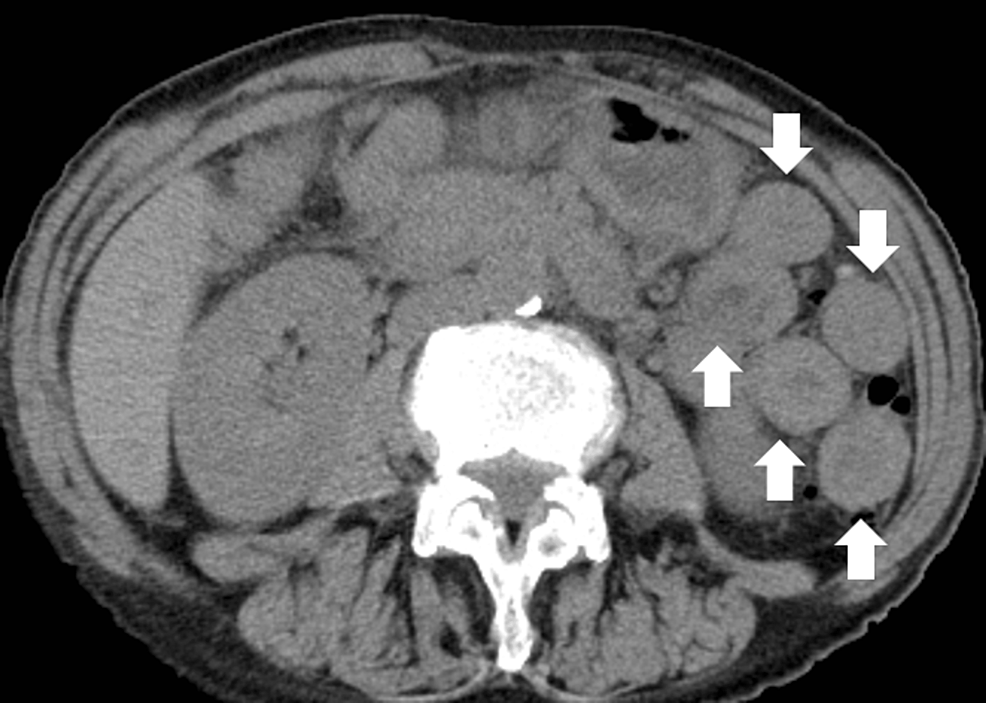

SCC in middle esophagus (mucosal invasion carcinoma in situ; depressed

SCC in middle esophagus (mucosal invasion carcinoma in situ; depressed What Causes White Plaques In Esophagus With this disease, a type of. This leads to difficulty swallowing and chest pain. Eosinophilic esophagitis (eoe) is a chronic inflammatory disease of the esophagus. We report a case of esophageal. Eosinophilic esophagitis is a condition in which certain white blood cells, called eosinophils, are found in the esophagus. In people with eoe, white blood cells called eosinophils build up. What Causes White Plaques In Esophagus.